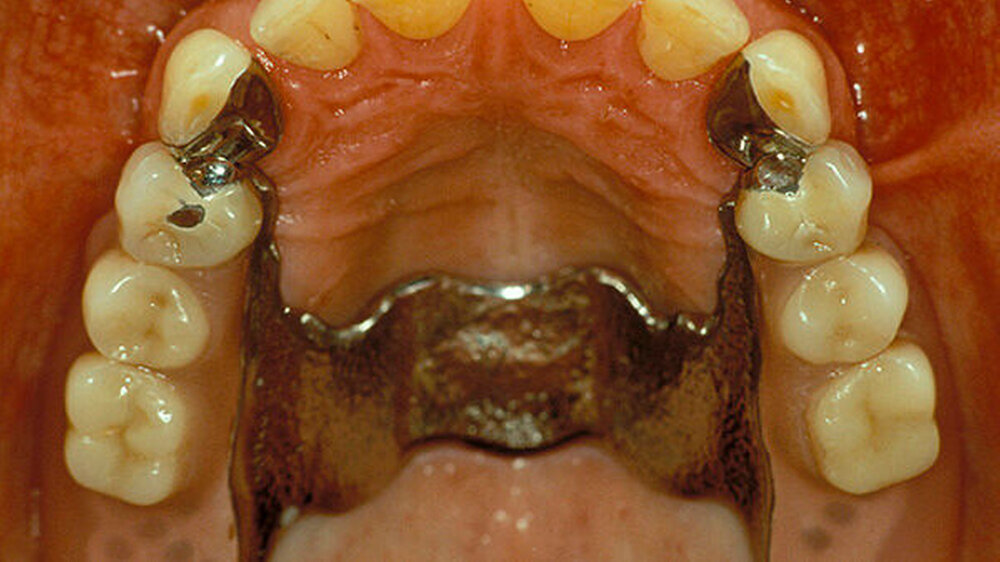

Beispiele für individuellen ZE

Die Jahrestagung der Deutschen Gesellschaft für Prothetische Zahnmedizin und Biomaterialien (PGPro) in Ulm geht der Frage nach, welche Versorgungskonzepte - mit guten Langzeitergebnissen - individuell und preiswert machbar sind. Gute Beispiele finden Sie in unserer Bilderstrecke!